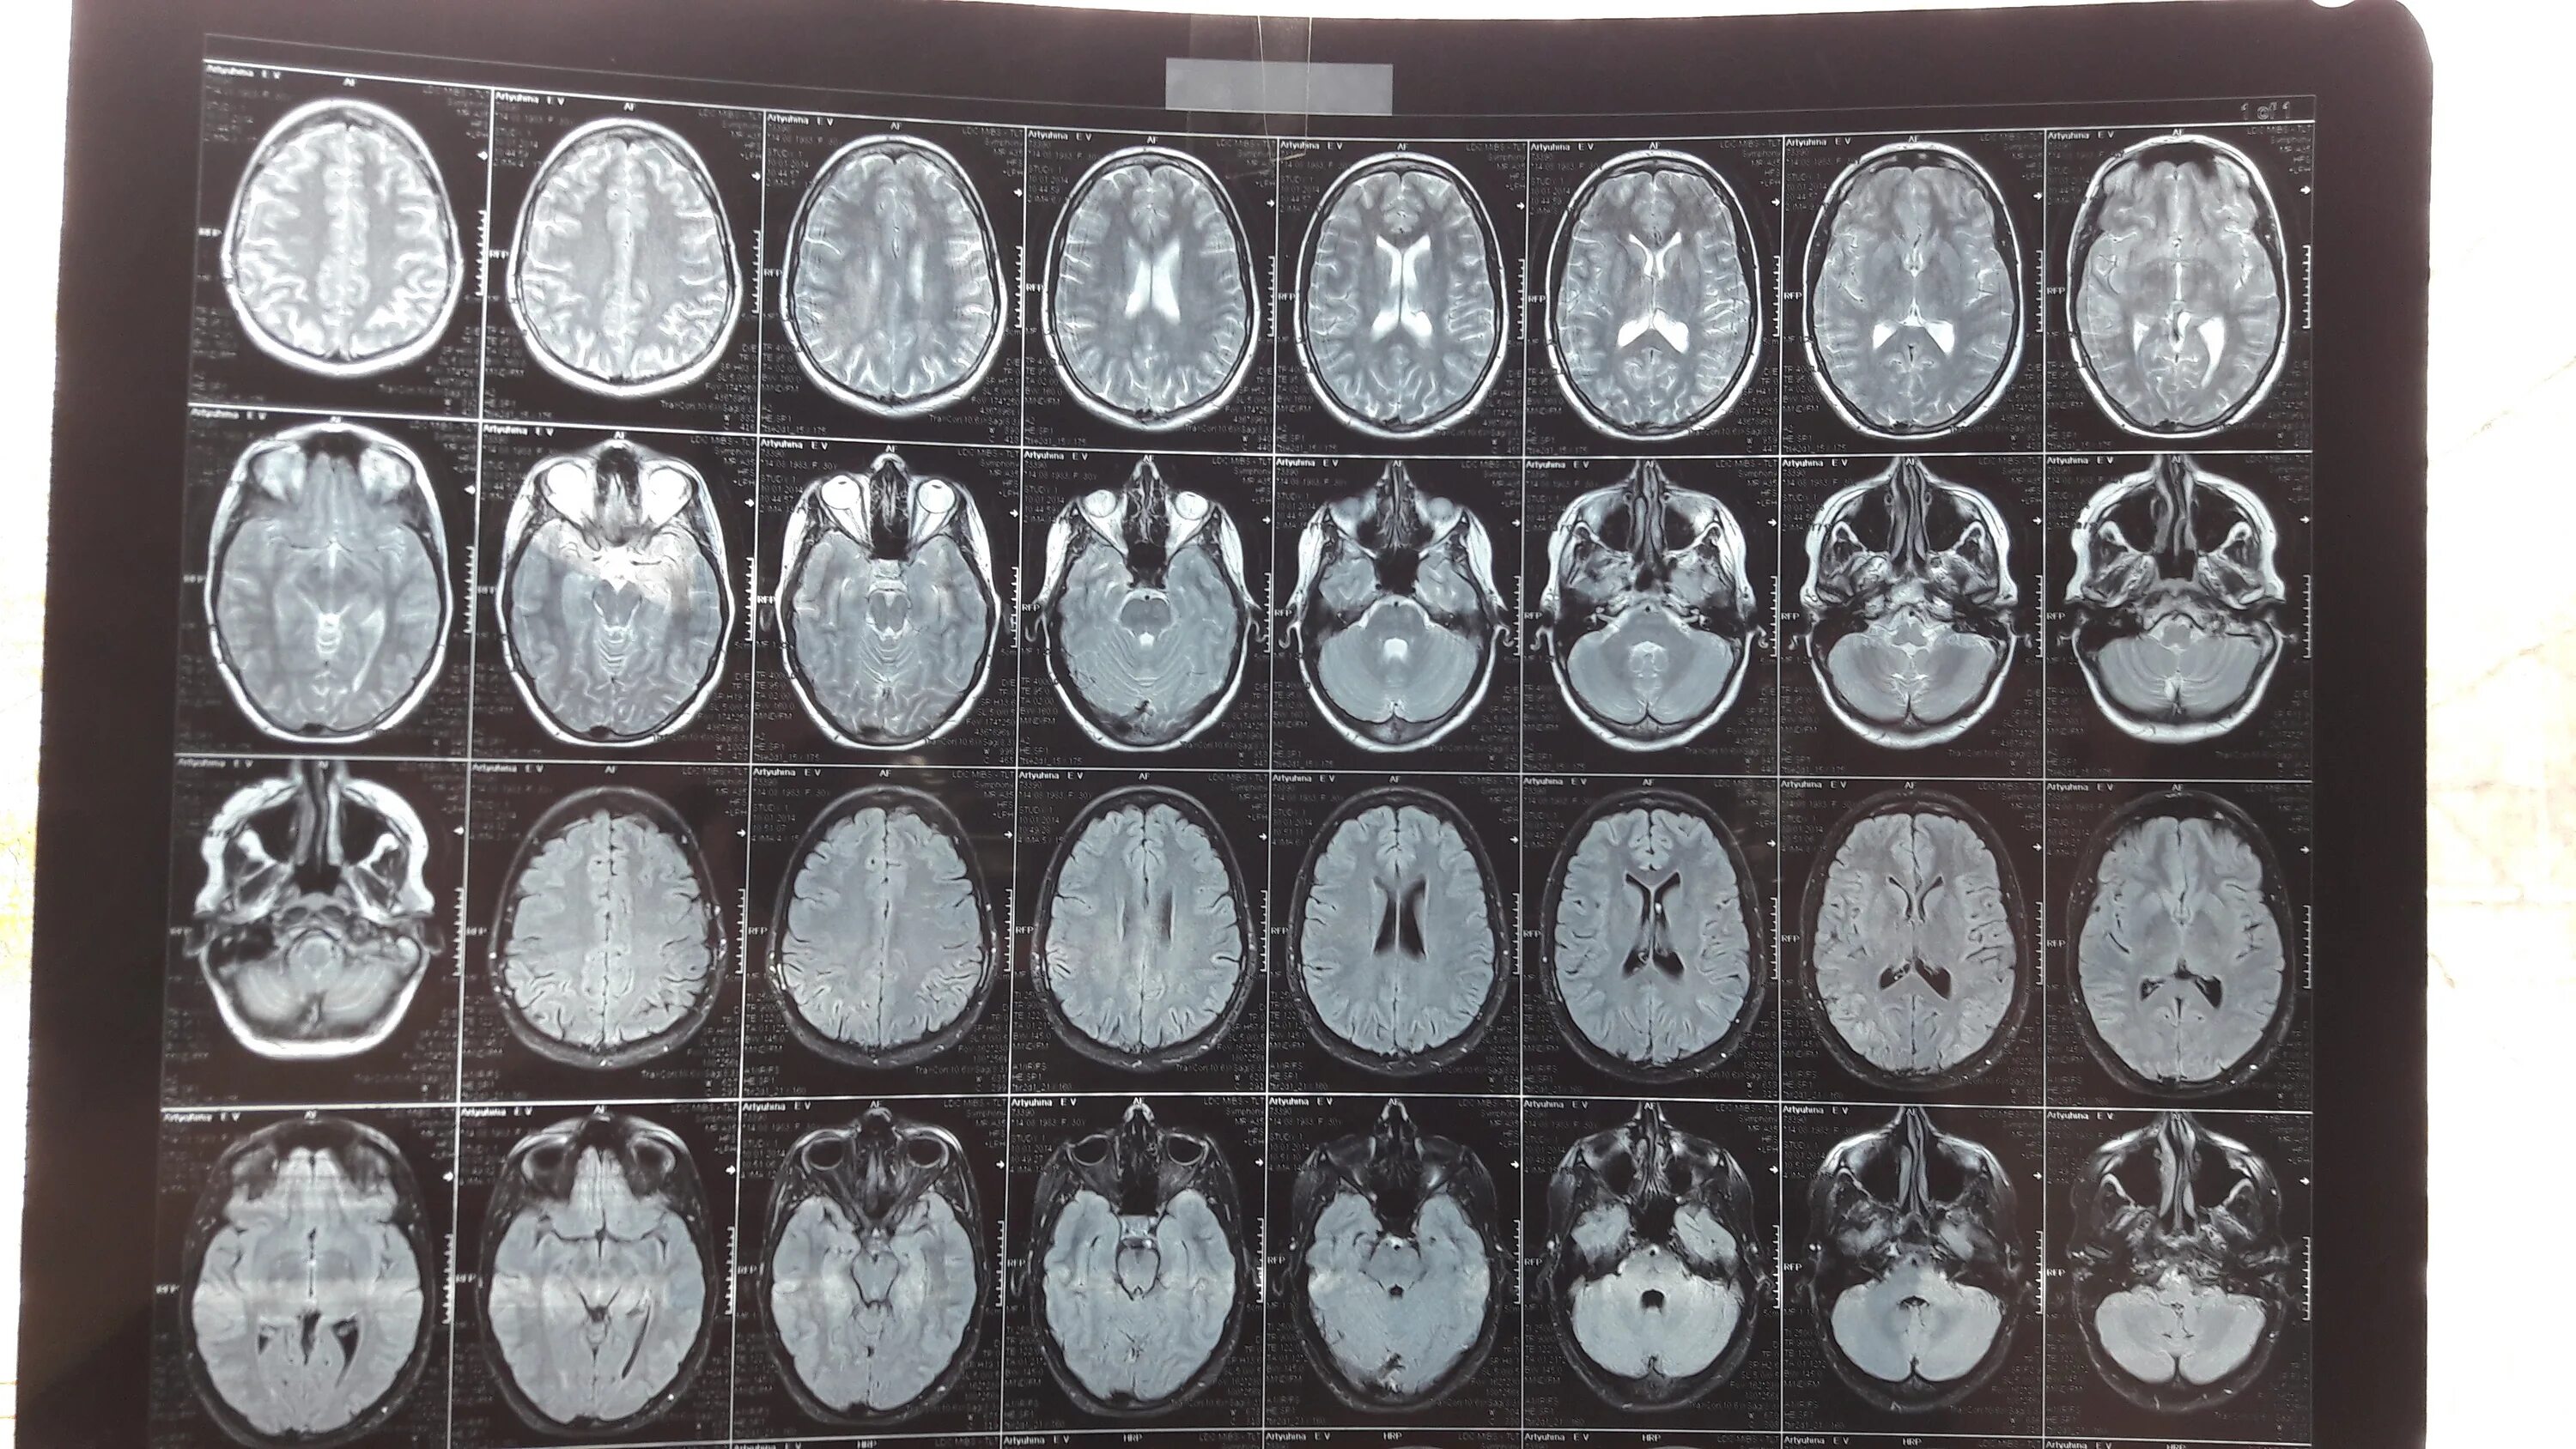

16 линия 81 мрт